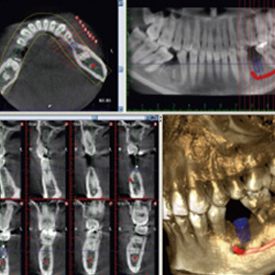

精度が高い診査・診断&安心・安全な治療歯科用CT- Computer Tomograghy -

CTとはComputer Tomograghyの略で、日本語ではコンピューター断層撮影と訳されます。

これは、X線とコンピューターによって、歯や骨の位置や形態などを3D画像で立体的に撮影するための医療機器です。

血管や神経の位置を立体的に把握し、骨量、骨密度を正確に確認できるため、インプラント治療の際にはCTによる診査・診断が必須となっています。

また、CTは、インプラント治療だけでなく、全ての歯科治療の精度向上に役立ちます。

歯槽骨の状態や根管の形態等をより正確に把握することができるため、埋伏歯抜歯、矯正治療、根管治療、歯周病治療など、さまざまな治療において、より正確な診査・診断、治療の高度化が期待できます。

多くの歯科医院では、CTを撮影するために外部のスキャニングセンターへ撮影に出向く必要がありますが、当クリニックでは院内にCTを設置しているため、レントゲンと同じように院内で撮影し、即座に診ることができます。